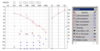

45-årig trommeslager i et heavy metal band, der ellers er sund og rask henvender sig til øre-næse- hals-lægen, da han har fået tiltagende problemer med at høre på venstre øre samt tinnitus på venstre øre. Han oplever desuden kortvarig ubalance, hvis han vender sig hurtigt rundt. Patienten har ikke slået hovedet, og han har ikke hovedpine.

Han får lavet nedenstående audiogram samt tympanometri.

1. Angiv supplerende spørgsmål til anamnesen (max 20 ord).

- Der skal spørges ind til erhvervsmæssig støjpåvirkning og varighed af denne samt arvelige høretab i familien.

- Fuldt point, hvis angivelse af: Støjanamnese, varighed og disposition til høretab.

Essay

45-årig trommeslager i et heavy metal band, der ellers er sund og rask henvender sig til øre-næse- hals-lægen, da han har fået tiltagende problemer med at høre på venstre øre samt tinnitus på venstre øre. Han oplever desuden kortvarig ubalance, hvis han vender sig hurtigt rundt. Patienten har ikke slået hovedet, og han har ikke hovedpine.

Han får lavet nedenstående audiogram samt tympanometri.

2. Hvilket type høretab er der tale om?

- Perceptivt asymmetrisk høretab.

- Fuldt point for angivelse af både asymmetri og perceptivt høretab.

- Angivelse af perceptivt høretab vigtigst.

Essay

45-årig trommeslager i et heavy metal band, der ellers er sund og rask henvender sig til øre-næse- hals-lægen, da han har fået tiltagende problemer med at høre på venstre øre samt tinnitus på venstre øre. Han oplever desuden kortvarig ubalance, hvis han vender sig hurtigt rundt. Patienten har ikke slået hovedet, og han har ikke hovedpine.

Han får lavet nedenstående audiogram samt tympanometri.

3. Angiv værdien af SRT for det højre øre og DS for det venstre øre incl. Enheder.

- SRT hø: 5 dB el. 5 dBHL – begge accepteres

- DS: 76 % (OK hvis de angiver værdier mellem 75-79%)

Essay

45-årig trommeslager i et heavy metal band, der ellers er sund og rask henvender sig til øre-næse- hals-lægen, da han har fået tiltagende problemer med at høre på venstre øre samt tinnitus på venstre øre. Han oplever desuden kortvarig ubalance, hvis han vender sig hurtigt rundt. Patienten har ikke slået hovedet, og han har ikke hovedpine.

Han får lavet nedenstående audiogram samt tympanometri.

4. Ang. en sandsynlig diagnose for det højresidige høretab.

Støj betinget høretab.

Essay

45-årig trommeslager i et heavy metal band, der ellers er sund og rask henvender sig til øre-næse- hals-lægen, da han har fået tiltagende problemer med at høre på venstre øre samt tinnitus på venstre øre. Han oplever desuden kortvarig ubalance, hvis han vender sig hurtigt rundt. Patienten har ikke slået hovedet, og han har ikke hovedpine.

Han får lavet nedenstående audiogram samt tympanometri.

5. Ang. en sandsynlig diagnose for det venstresidige høretab

- Sandsynligt retrocochleært høretab – muligt vestibularis schwanom/acusticus neurimom eller høretab af ukendt årsag.

- Perceptivt høretab som svar kan accepteres med 1 ud af 2 point, men det er mindre præcist end eks. retrocochleært høretab, der bør mistænkes her og derfor anføres som svar.

Essay

45-årig trommeslager i et heavy metal band, der ellers er sund og rask henvender sig til øre-næse- hals-lægen, da han har fået tiltagende problemer med at høre på venstre øre samt tinnitus på venstre øre. Han oplever desuden kortvarig ubalance, hvis han vender sig hurtigt rundt. Patienten har ikke slået hovedet, og han har ikke hovedpine.

Han får lavet nedenstående audiogram samt tympanometri.

6. Hvad er de forventede fund ved otoskopi på højre og venstre øre (max 10 ord)?

- Normalt udseende trommehinde eller intakt trommehinde på begge ører.

- Bemærkning om at venstre sides kan være let atrofisk pga. øget compliance accepteres

Essay

45-årig trommeslager i et heavy metal band, der ellers er sund og rask henvender sig til øre-næse- hals-lægen, da han har fået tiltagende problemer med at høre på venstre øre samt tinnitus på venstre øre. Han oplever desuden kortvarig ubalance, hvis han vender sig hurtigt rundt. Patienten har ikke slået hovedet, og han har ikke hovedpine.

Han får lavet nedenstående audiogram samt tympanometri.

7. Giv forslag til supplerende udredning og undersøgelse af patienten (max 20 ord).

- MR-scanning af fossa posterior/hørenerver

- Også OK at skrive cerebrum og/eller ABR- undersøgelse hjernestammeaudiometri samt vestibulærundersøgese eks. vHiT, og undersøgelse af kranienerver/otoneurologisk undersøgelse.

- Vigtigst er MR.

- ABR = Auditory Brainstem Response*

- VHIT = Video Head Impulse Test*

- Skema med pointgivning vedlagt på dette sidste delspørgsmål*.